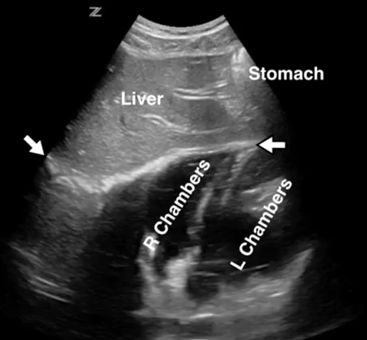

Pericarde (sous-Xiphoide)

Epanchement péricardique